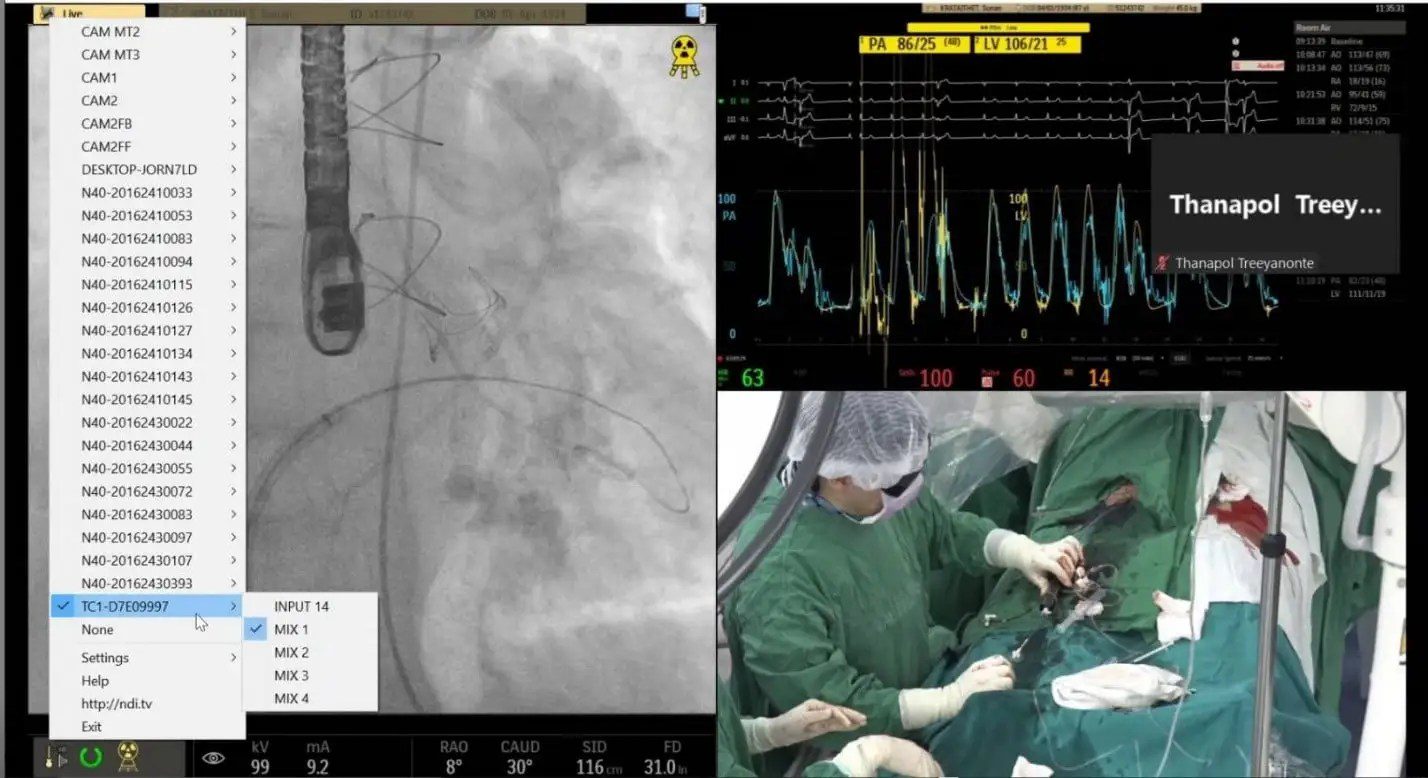

최고 수준의 의료 서비스를 제공하고 의대생, 심장 전문의, 내과의사 및 기타 의료진에게 교육과 훈련을 제공하는 것을 사명으로 하는 태국 방콕의 한 대형 병원은 TriCaster® 및 NDI® 기반의 강력한 비디오 솔루션을 사용하여 수술실에서 수술 과정을 시연하고 있습니다.

병원 측은 이후 수술실 카메라의 실시간 영상과 수술 중 동시에 사용되는 다양한 의료 기기의 데이터를 스트리밍할 수 있는 완전히 새로운 접근 방식을 개발했습니다. 기존 회의 시스템과는 달리, 이 솔루션은 Vizrt의 실시간 영상 제작 및 스트리밍 솔루션, 예를 들어 TriCaster® TC1 및 TriCaster Mini 4K를 기반으로 합니다 . 이러한 사용하기 쉬운 영상 제작 시스템을 통해 전문적인 영상 제작이나 IT 지식이 없는 사람이라도 방송 품질의 영상과 최대 UHD 해상도의 영상을 제작할 수 있습니다.

병원은 독자적인 영상 제작 시스템을 갖추고 수술실 두 곳에 NDI 호환 비디오 카메라를 전략적으로 설치했으며, 가까운 시일 내에 세 번째 수술실에도 설치할 계획입니다. iPad, 노트북 또는 컴퓨터 키보드를 사용하여 NDI 카메라의 영상 신호를 미리 설정, 제어, 전환하고 병원 회의실에 표시하거나 Zoom과 같은 플랫폼을 통해 온라인 회의에 통합할 수 있습니다. 영상 신호는 TriCaster 스위처로 바로 스트리밍할 수도 있고, 필요에 따라 이러한 IP 기반 도구를 사용하여 팬, 틸트, 줌 기능을 포함한 카메라 원격 제어도 가능합니다. 이는 태국 병원에서 진행 중인 심장 교육 및 상담 실시간 스트리밍 프로젝트의 일환입니다.

수술실 의료기기의 데이터는 iPad, 노트북 또는 컴퓨터 인터페이스를 사용하여 원격으로 관리 및 제어할 수 있습니다. 의료 장비의 HDMI 및 DVI 출력은 양방향 4K 변환기를 사용하여 실시간으로 NDI로 변환되어 최대 4K/60p 해상도로 네트워크를 통해 전송됩니다.

Vizrt 기반 솔루션 덕분에 병원은 그 어느 때보다 간편하게 영상 제작을 할 수 있게 되었습니다. 병원에서는 이 솔루션을 주 5일, 하루 8~10시간씩 문제없이 사용하고 있습니다. 여러 대의 NDI 비디오 카메라와 8~10대의 의료 기기에서 나오는 신호를 TriCaster 스위처로 전송할 수 있도록 기술, 도구 및 네트워크가 영구적으로 설치되어 있습니다. 이러한 시스템과 두 개의 수술실, 그리고 인접한 회의 공간 모두 NDI 네트워크에 연결되어 있습니다. 병원에서 세 번째 수술실과 기타 의료 장비를 추가할 계획이므로, Vizrt 시스템은 병원의 성장에 맞춰 확장될 예정입니다.